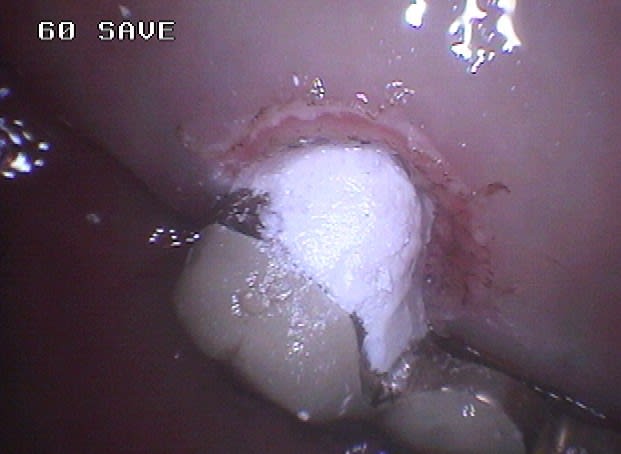

Voici un cas moins gentil avec élimination de la cause du problème pour reprendre les termes de Marc.

Il s'agit d'une patiente de 90 ans sur qui je reconstituais les secteurs postérieurs mandibulaires, ce qui fera l'objet d'un prochain post d'ailleurs, et dont un simple détartrage révélait la présence d'une énorme carie sous le pilier distal d'un bridge reliant la 23 à la 26.

Ayant intérêt à éviter de commencer un gros chantier alors qu'un autre était en cours, j'ai opté pour dégager et éliminer cette carie en conservant provisoirement ce bridge qui tenait bien, avant de traiter ce secteur en tachant de récupérer la racine de la 26 si possible.